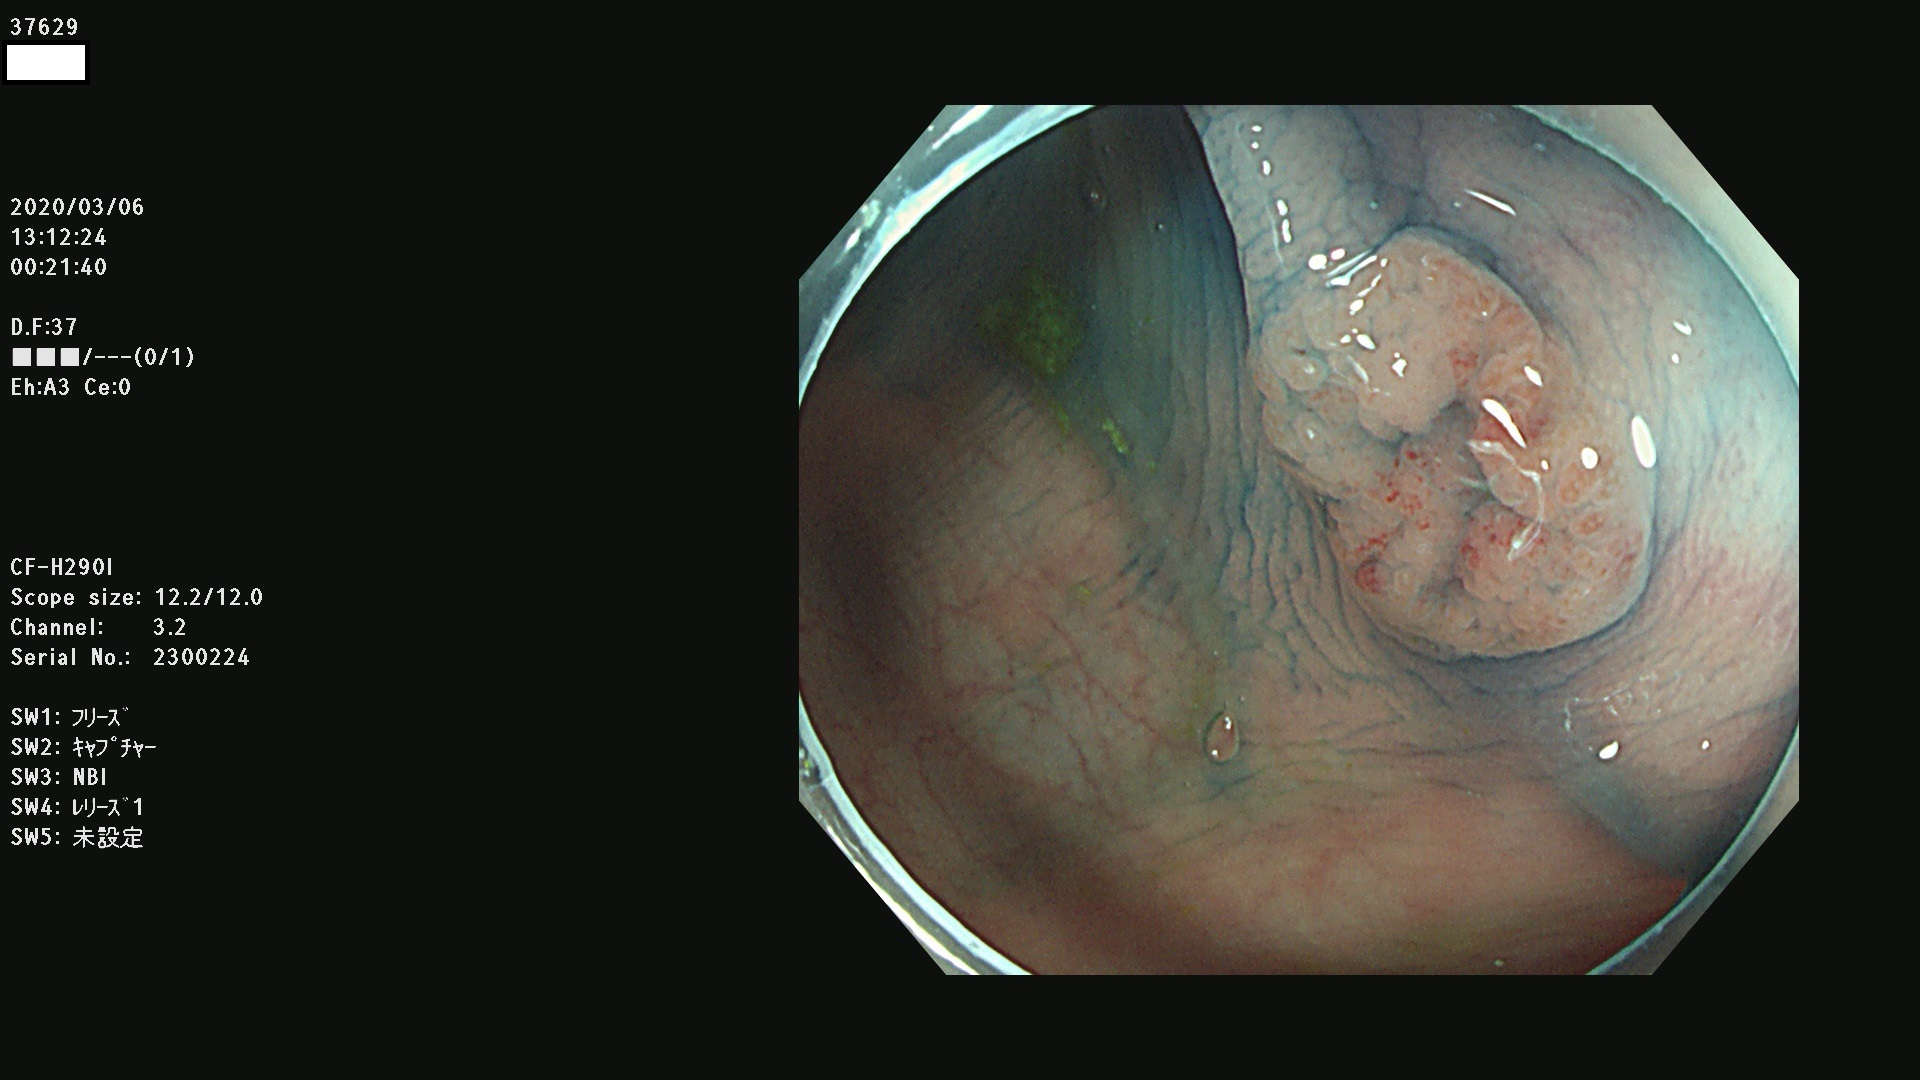

37600 37601 37602 37603 37604 37605 37606 37607 37608 37612 37614 37616 37618 37619 37620 37621 37622(SSAPのみ) 37623(SSAPのみ) 37624 37626 37627 37628 37629 37632 37633 37635 37636(SSAPのみ) 37639 37640 37641 37642 37643 37644 37647(SSAPのみ) 37648 37649 37650 37652 37653 37655 37657 37659 37660 37662 37664 37666 37668(SSAPのみ) 37670 37671 37672 37676 37677 37678 37679 37680 37682 37684 37685(SSAPのみ) 37686 37687 37688 37689 37690 37691 37692(SSAPのみ) 37693 37694 37695 37696 37697 37699

発見困難で危険性の高い平坦型病変(上記100名より抽出)